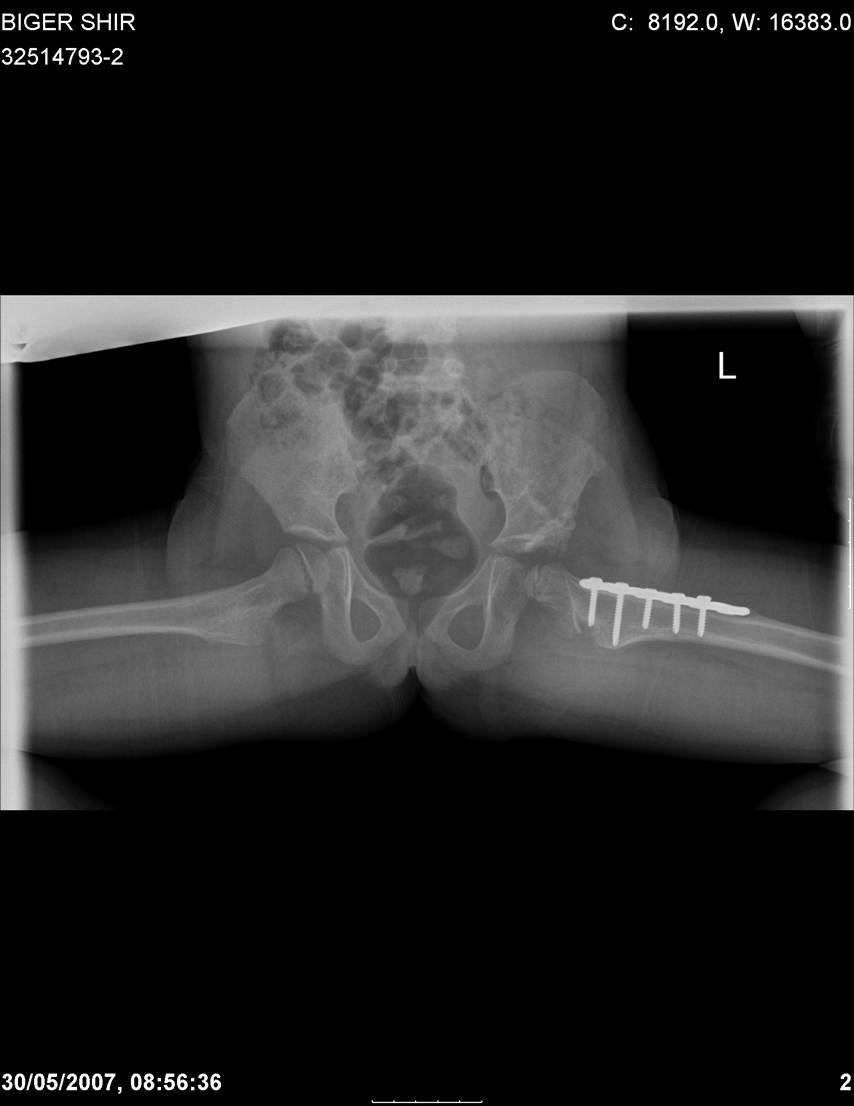

Navernoe Dega

Chto by ne byt goloslovnym posilau vam svoi sluchai gde sdelal vse chto napisal vyshe

Mark Eidelman